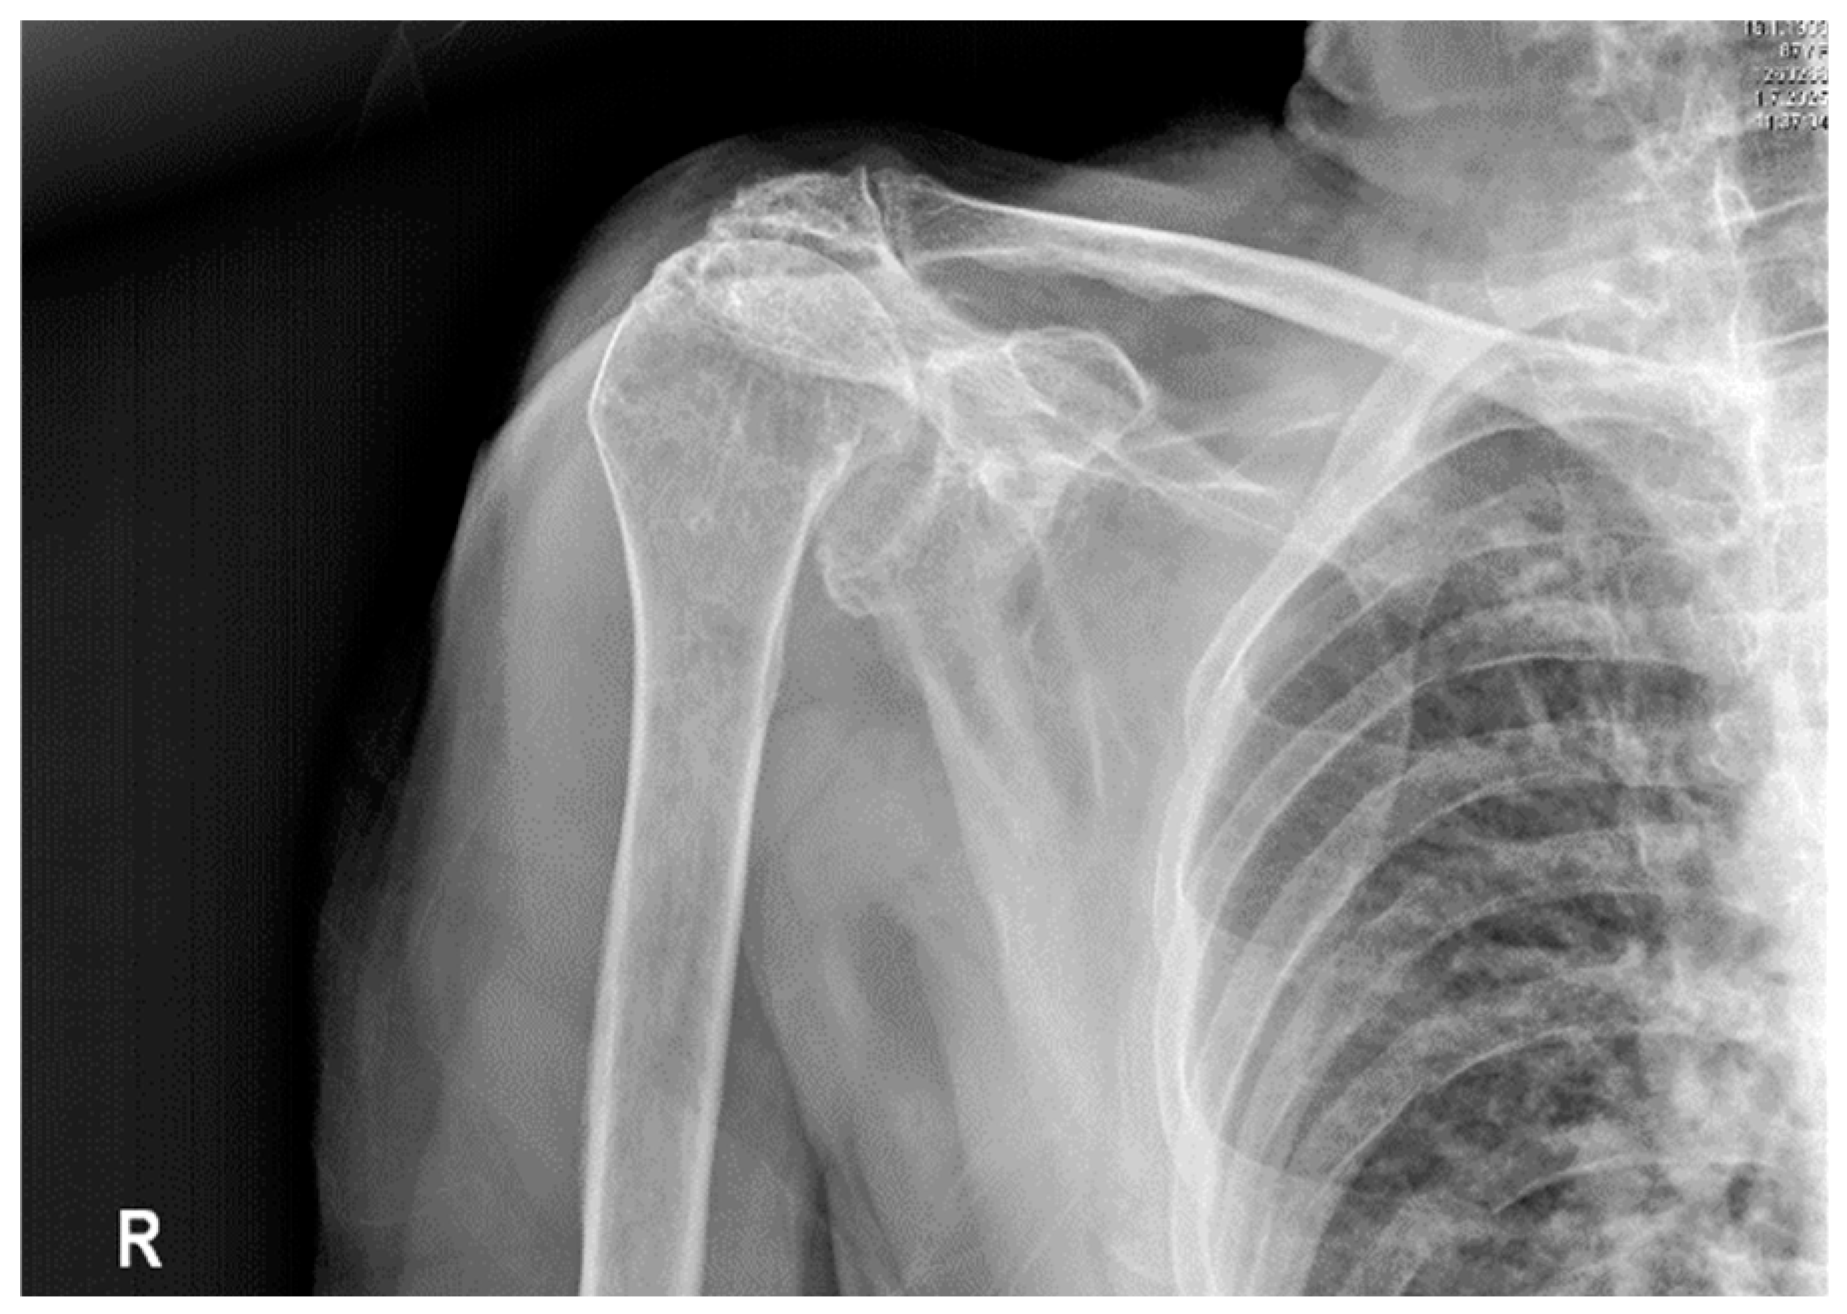

- Musculoskeletal disorders, such as omarthrosis, can conceal severe vascular conditions, necessitating an interdisciplinary approach to diagnosis. Clinicians should be aware that common issues like degenerative joint disease might coexist with or hide life-threatening vascular problems. An interdisciplinary approach combined with careful physical examination is vital to prevent misdiagnosis.